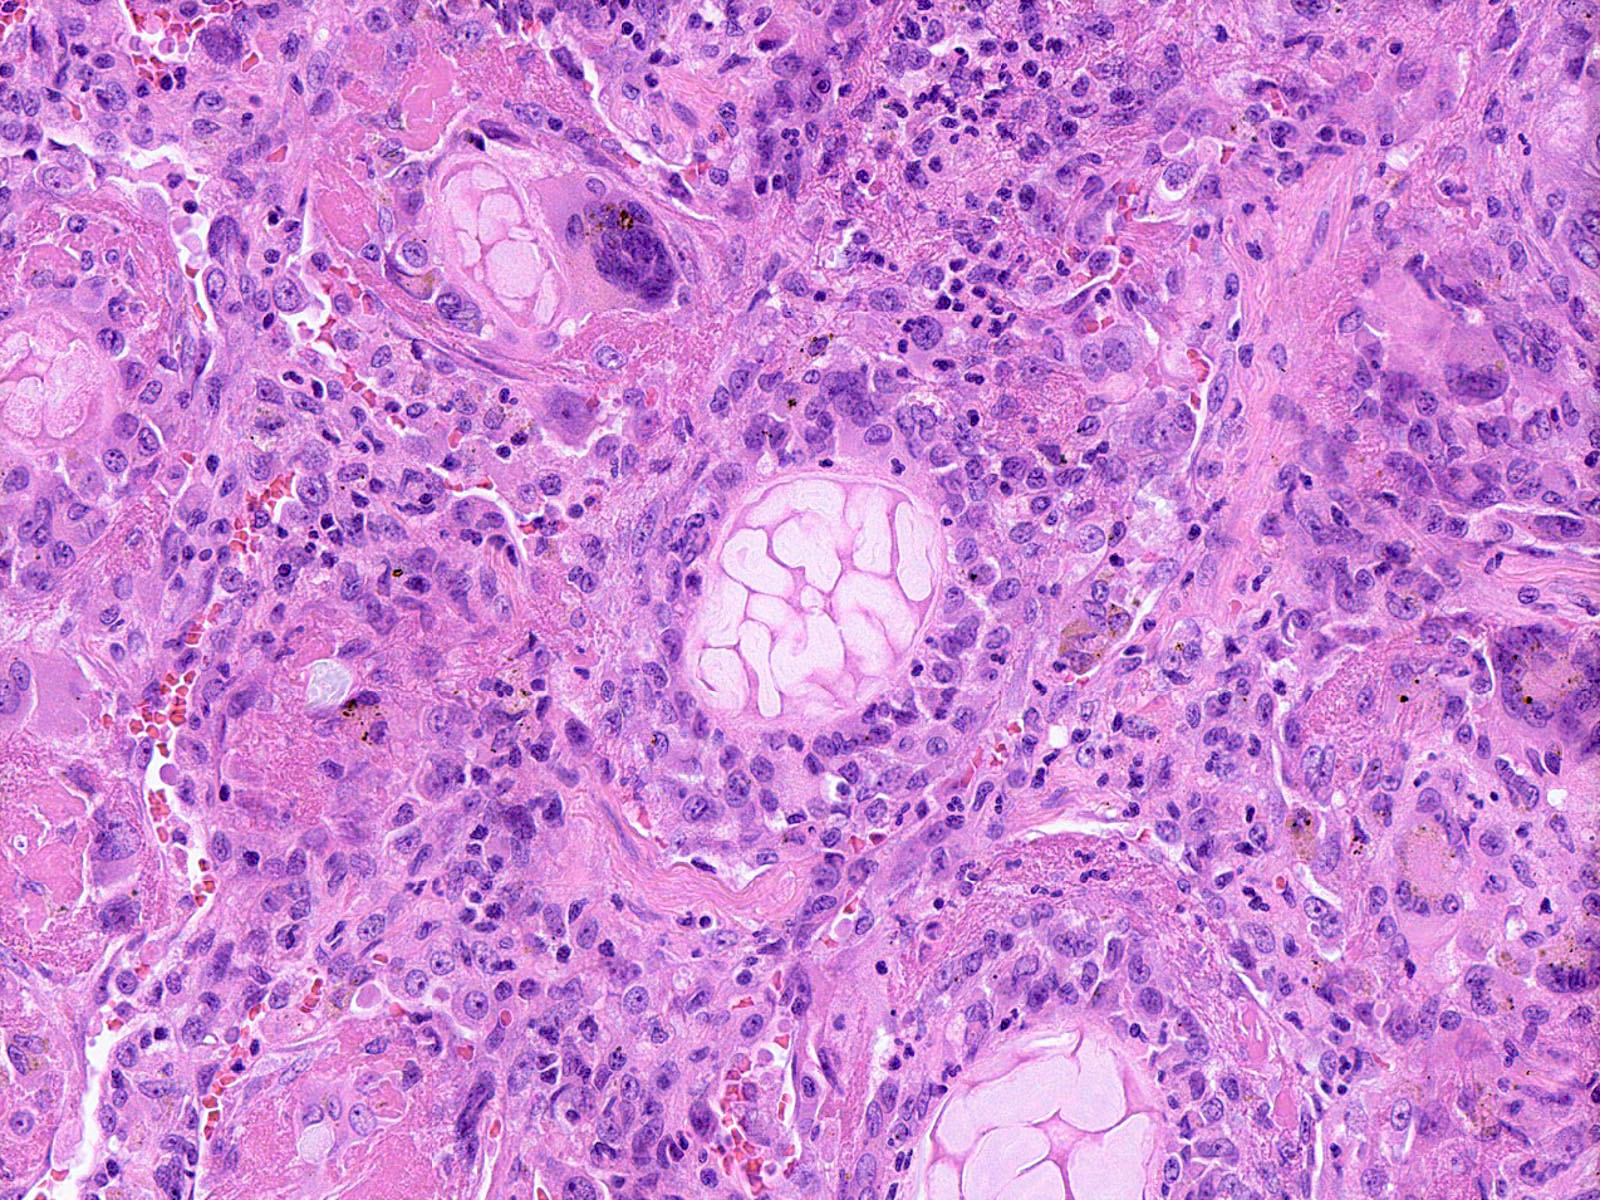

Microscopic (histologic) description

- Bronchopneumonia:

- Most common pattern of pulmonary infection

- Different stages in the different areas

- Patchy intra-alveolar fibrinopurulent exudate with neutrophils

- Necrotizing pneumonia (Can Respir J 2014;21:239):

- Characterized by necrotizing inflammation, leading to alveolar septa disruption and cavity formation

- Common organisms: Staphylococcus aureus, Streptococcus pyogenes, S. pneumoniae (certain serotypes), Klebsiella, Acinetobacter, Pseudomonas and Burkhodoria

Microscopic (histologic) images